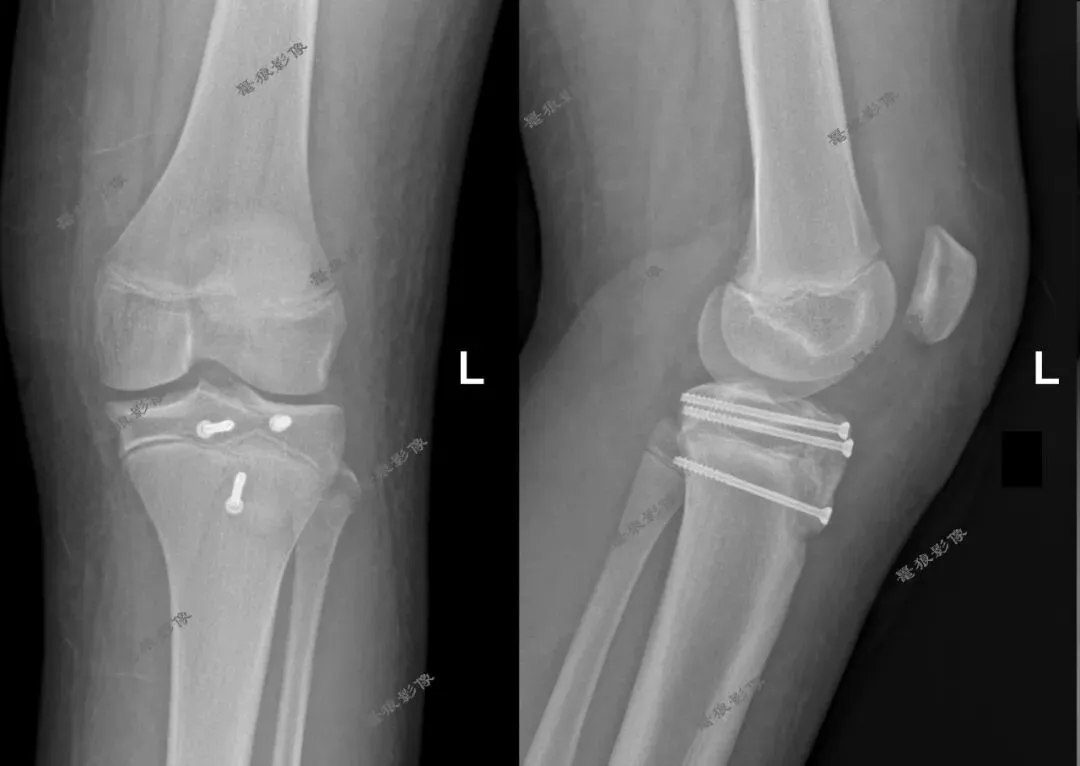

M,11y。

缘患者入院3小时余前运动后出现左膝部疼痛,活动受限,当时无昏迷,遂送至急诊就诊,查X片:左胫骨结节骺离骨折。

一.术前X线片

3.术后X线片:

4.术后CT: